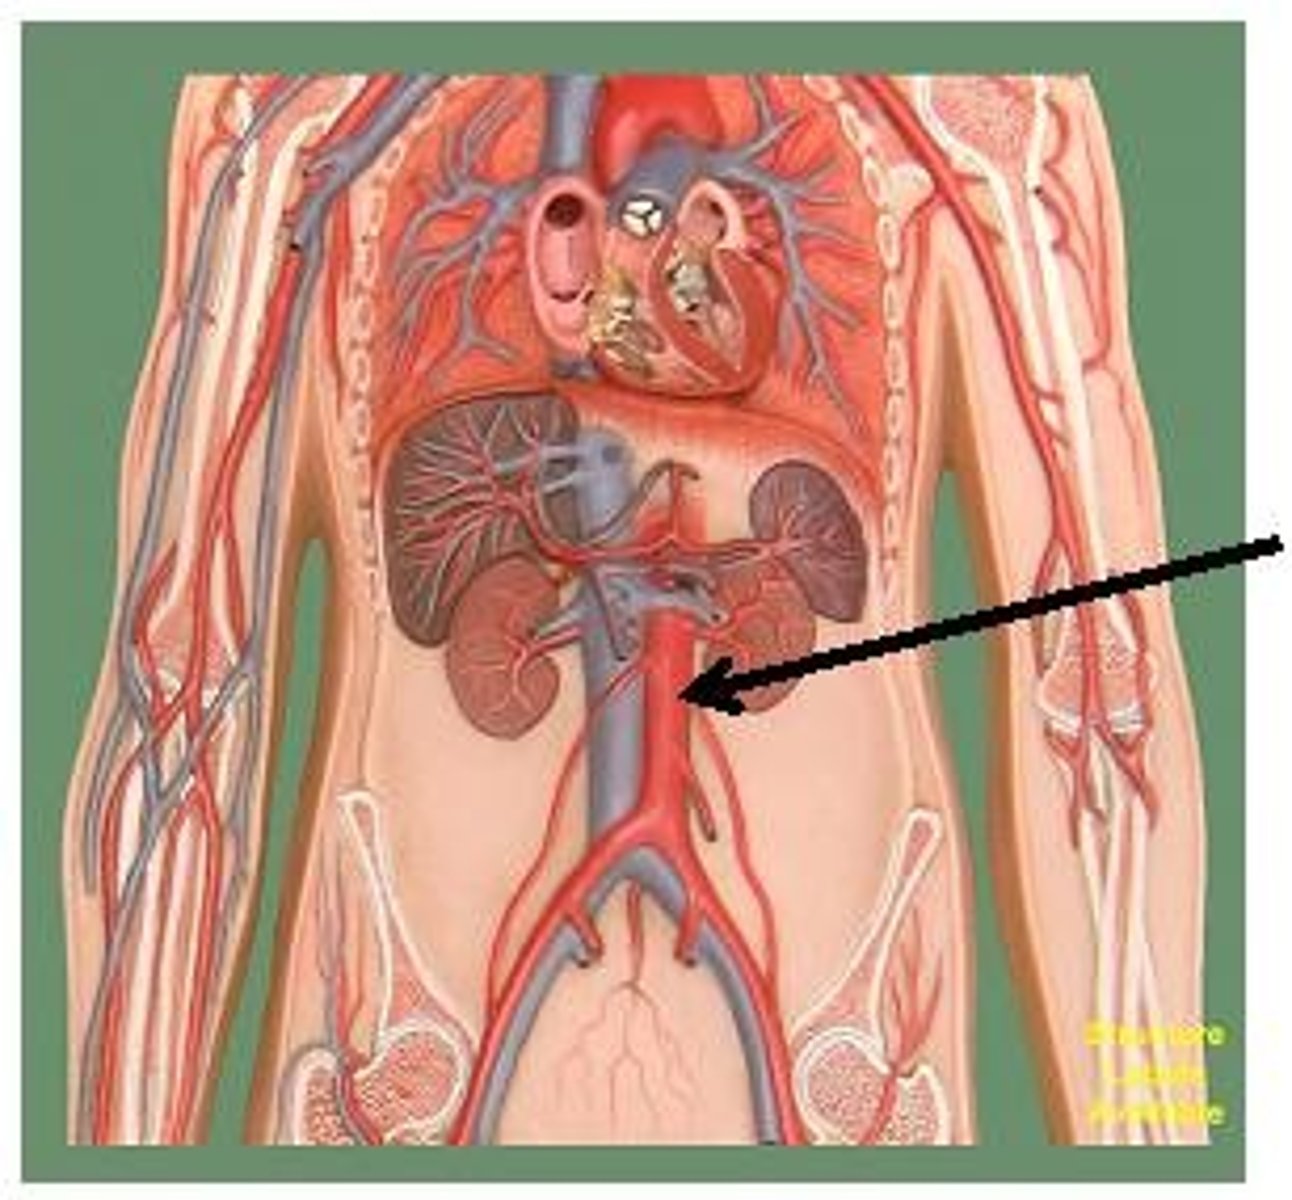

abdominal aorta

renal artery

serves the kidneys

gonadal artery

serves reproductive organs

iliac artery

Serves the pelvic organs, lower abdominal wall, and lower limbs